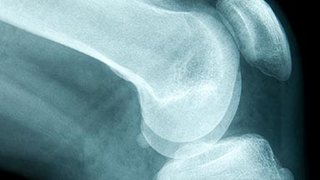

X-ray of pelvis and hips.

Preoperative radiograph showing bilateral hip dysplasia.